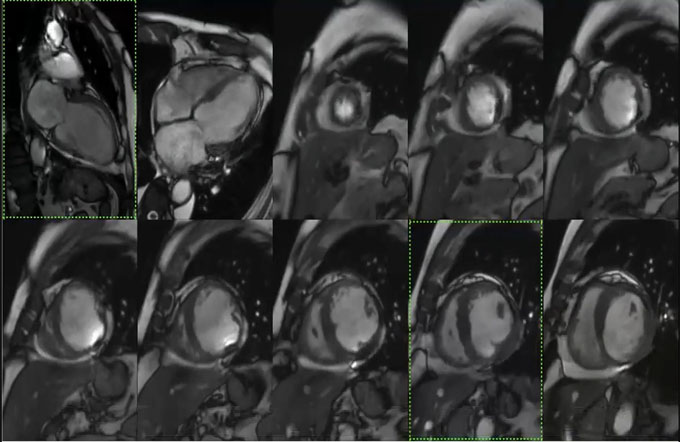

RADIOLOGY EDUCATION FOUNDATION